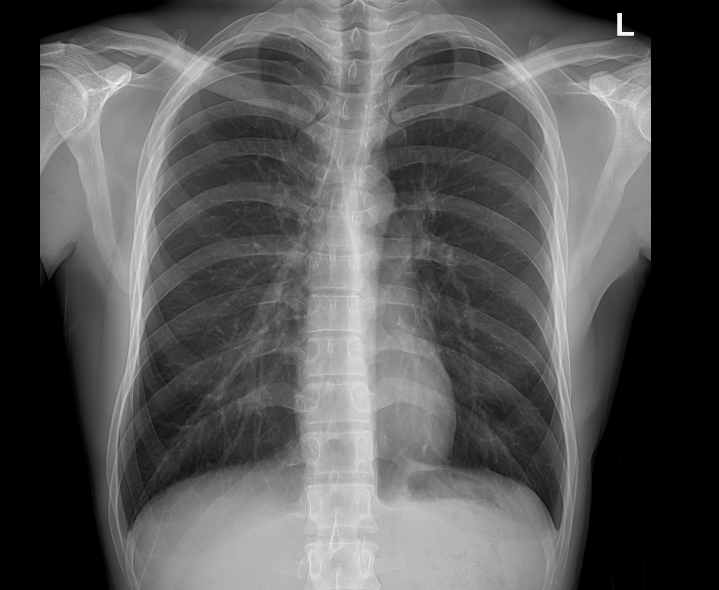

• Clinical Images